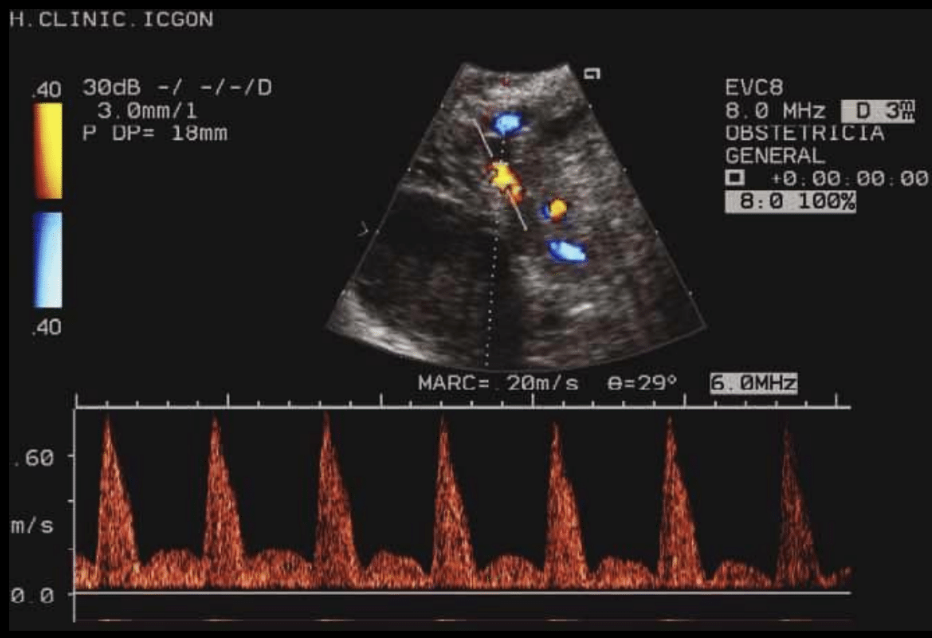

Usos del doppler en arteria oftálmica

Embarazadas, para evaluar riesgo de preeclampsia

Riesgos en pacientes con falla cardiaca